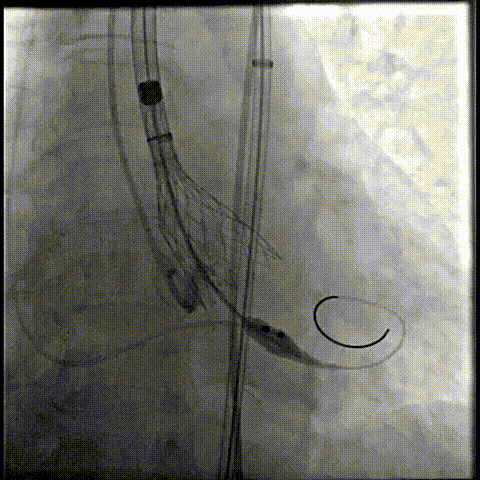

释放瓣膜

80%工作位评估

精准释放:该病例室间隔膜部较短,需精准释放到位,减少PPI发生可能性;其底部桶状设计更易迅速锚定,协同释放张力小,助力最终精准释放;